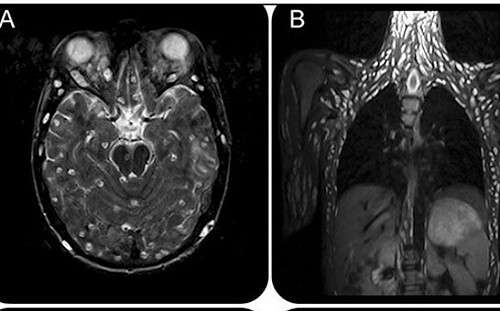

吃生豬肉抽蓄「感官扭曲」!男子就醫檢查驚見「全身長滿寄生蟲」